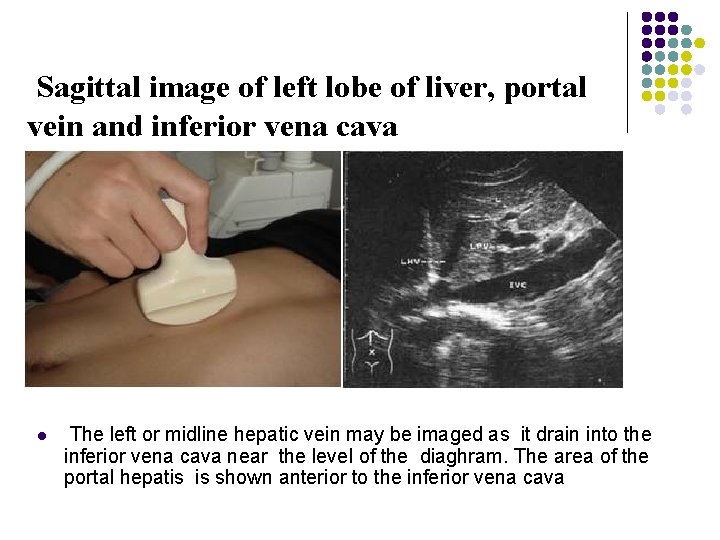

Longitudinal Scan Plane l l Scan Ⅱ As the sonographer scans at midline or slightly to the right of midline , a larger segment of the left lobe and the inferior vena cava may be seen posteriorly. In this view , it is useful to record the inferior vena cana as it is dilated near the end of inspiration. The left or midline hepatic vein may be imaged as it drain into the inferior vena cava near the level of the diaghram. The area of the portal hepatis is shown anterior to the inferior vena cava as the superior mesenteric vein and splenic vein converge to form the main portal vein. The common bile duct may be seen just anterior to the main portal vein. The head of the pancreas may be seen just inferior to the right lobe of the liver and main portal vein and anterior to the inferior vena cava.

Sagittal image of left lobe of liver, portal vein and inferior vena cava l The left or midline hepatic vein may be imaged as it drain into the inferior vena cava near the level of the diaghram. The area of the portal hepatis is shown anterior to the inferior vena cava